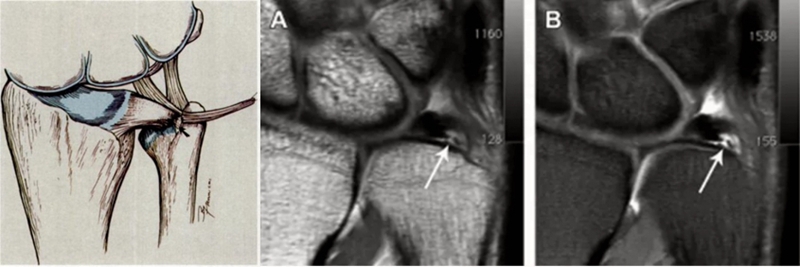

Case1

女性,42岁,右腕疼痛1年+,2020年4月手术。

影像学检查

关节镜视频

关节镜下清理后